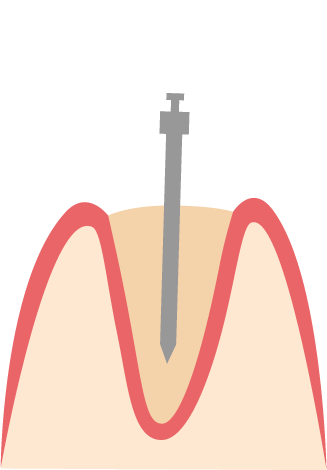

Zahnkrone mit Stiftaufbau